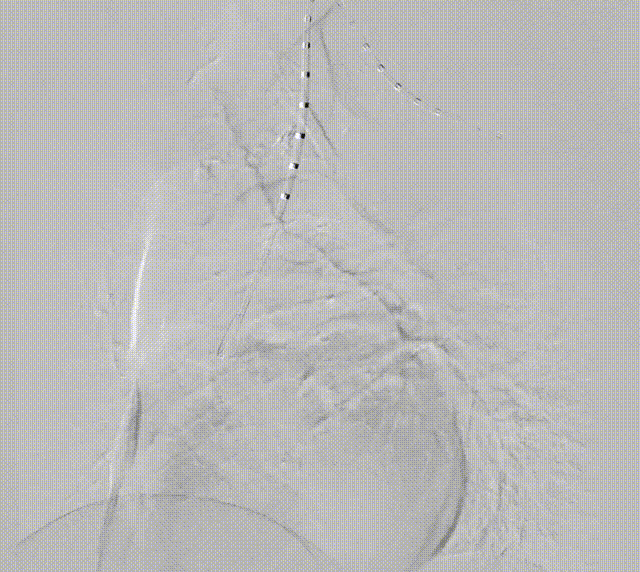

●術(shù)中(zhong)造(zao)影:

造(zao)影可(kě)見明顯潰瘍位置

沿預埋導(dao)絲(si)推送支架主(zhu)體(ti)至預期位置

支架對位準确、LSA分(fēn)支通(tong)暢

釋放分(fēn)支支架,可(kě)見病變安(an)全覆蓋(gai),支架定位準确,LSA分(fēn)支通(tong)暢,無內(nei)漏,效果滿意